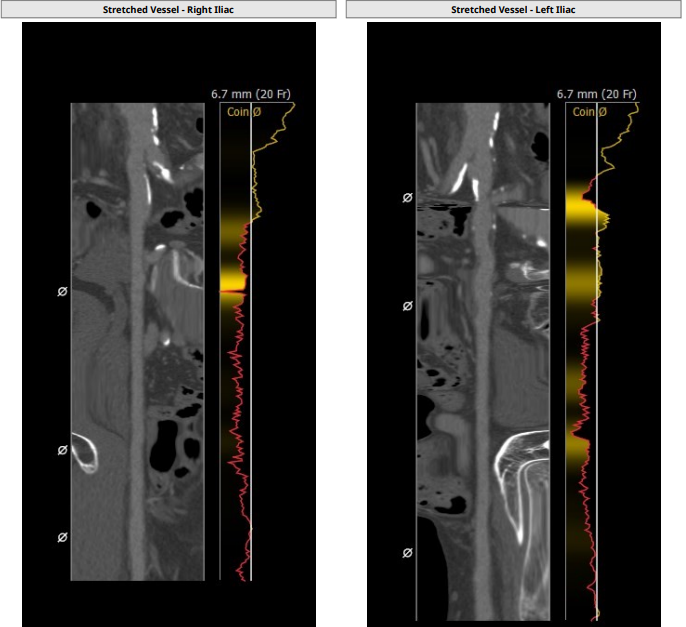

入路情况:

主动脉弓部走行欠佳,主动脉弓部三根毛开口未见明显狭窄征象、未见发育变异,胸主动脉、腹主动脉走行迂曲、未见明显钙化斑块,管腔未见明显狭窄,双侧髂动脉-股动脉走形稍迂曲,管腔未见明显狭窄,综合考虑,推荐右侧股动脉做为主入路。右侧股动脉穿刺水平管腔直径约为 8.2 mm,右侧股动脉分叉约在股骨头下缘水平。